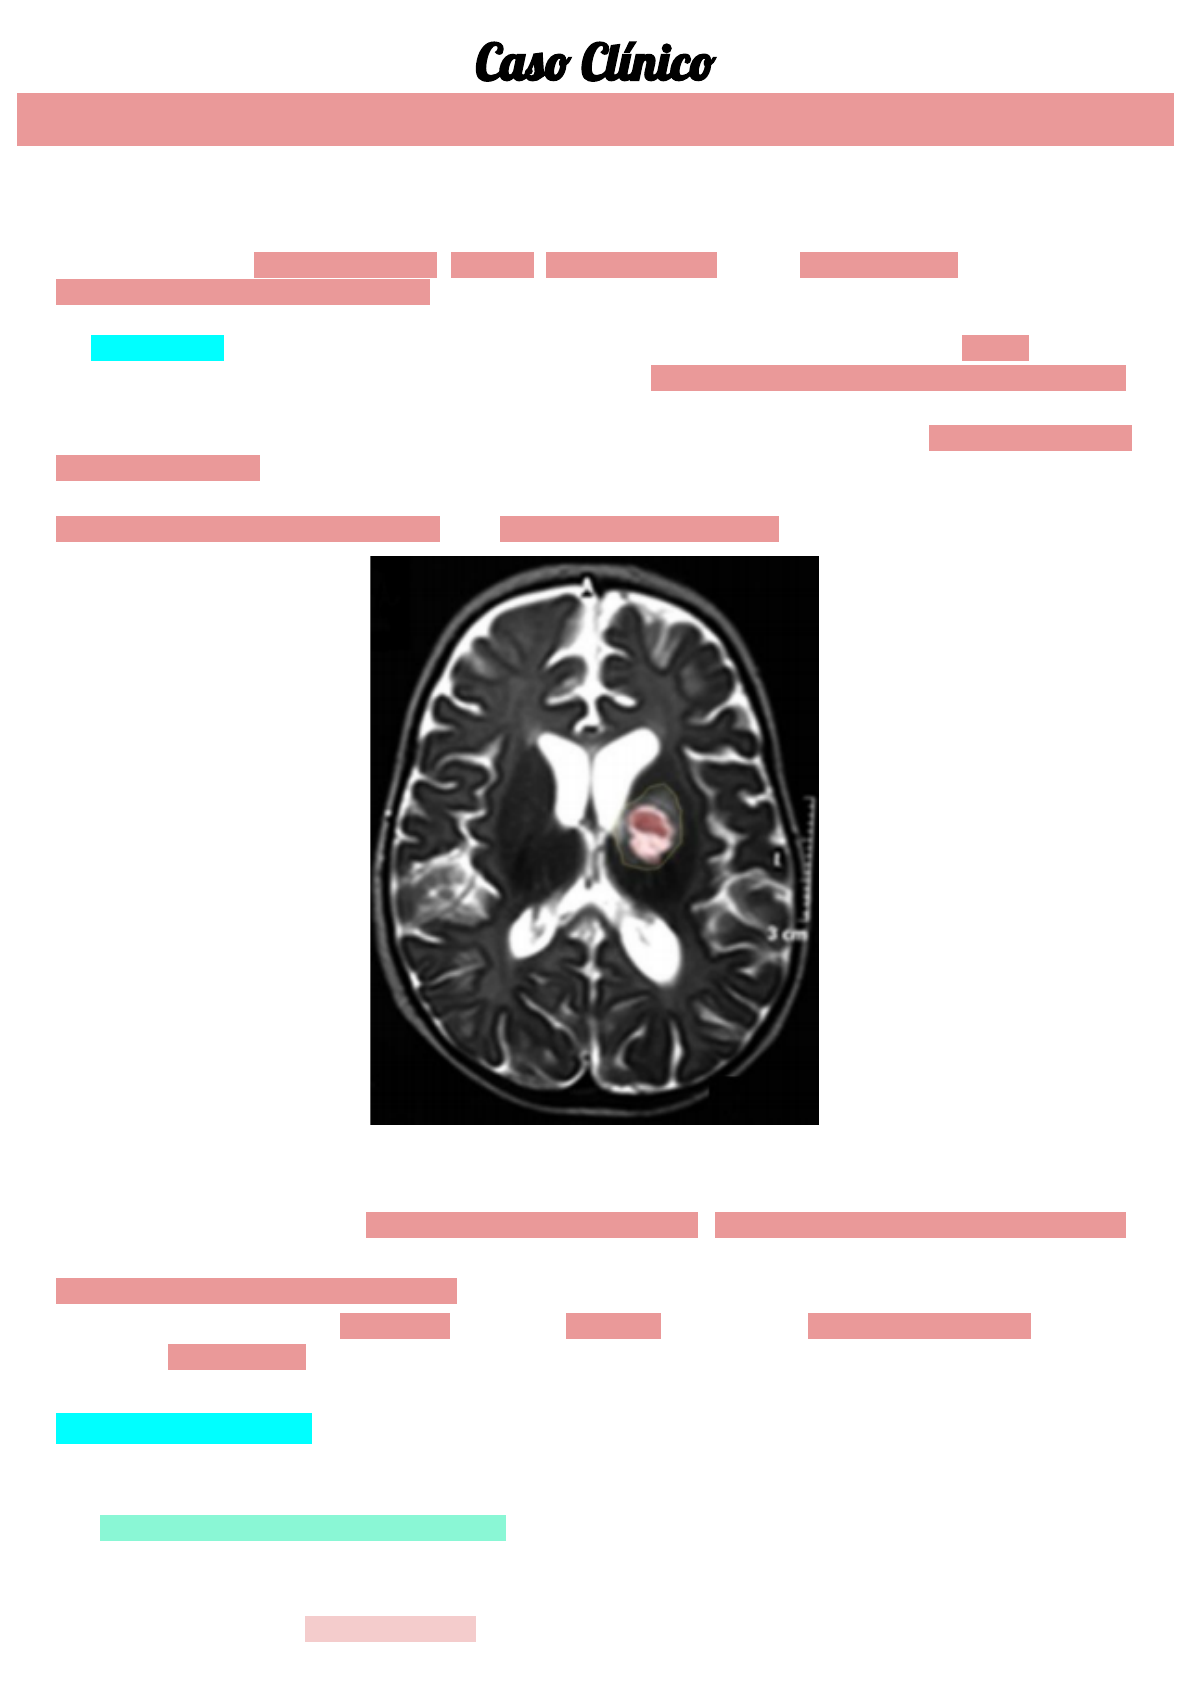

Foi solicitada a punção lombar, exames de imagem (RNM) e hemocultura. Inicialmente, a RNM evidenciou

abscesso cerebral e empiema subdural, com suspeita de lesão de massa (Figura 1).

Figura 1: RNM de crânio, em corte axial, mostrando lesão hipodensa mais acentuada em giro temporal superior direito, área de

abscesso cerebral no joelho da cápsula interna esquerdo, na borda anterior do putamen e cabeça do núcleo caudado, além da

dilatação do sistema ventricular.